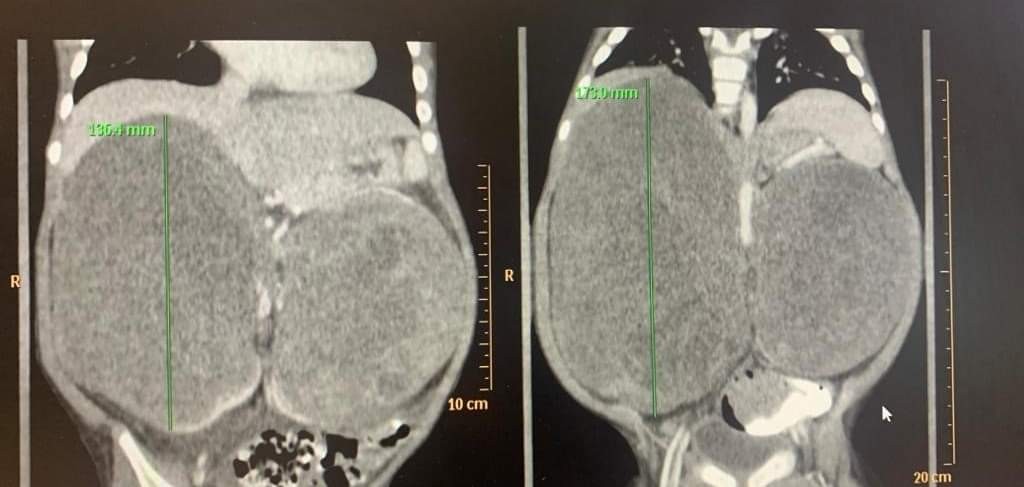

Lekári Národného ústavu detských chorôb (NÚDCH) chlapčekovi odstránili dva veľké obojstranné nádory na obličkách. Jeden z nich vážil 1,3 kilogramu a pacientovi tlačil na bránicu a pľúca. Lekárom sa podarilo zachrániť aj obličku. Informovala o tom hovorkyňa NÚDCH Dana Kamenická.

Po konzultáciách so zahraničnými špecialistami v Holandsku a USA sa ukázalo, že je nutné zrealizovať vysoko náročné a rizikové operácie. "Na CT vyšetrení sme videli obojstranný veľký nádor na obličke, ktorý tlačil na bránicu a boli utláčané pľúca. Dieťatko už začínalo mať problémy s dýchaním. Rozhodli sme sa pre urgentnú operáciu," ozrejmil riaditeľ NÚDCH a operujúci lekár Peter Bartoň.

Pacient po tom, ako mu úspešne vybrali prvý tumor, nastúpil na onkologickú liečbu. "Chemoterapiou sa lekárom podarilo takmer rovnako veľký tumor na druhej obličke zmenšiť a približne po roku od prvej operácie čakal chlapčeka druhý operačný výkon," priblížila hovorkyňa NÚDCH.

Po úspešnej operácii má detský pacient všetky obličkové parametre v poriadku. "Táto operácia bola pre nás skutočnou chirurgickou výzvou, akú radi prijímame. Išlo o operáciu na hranici technických možností s neobvykle komplikovanou rekonštrukciou zvyšku obličky po odstránení tumoru," dodal prednosta kliniky pediatrickej urológie Ján Breza.